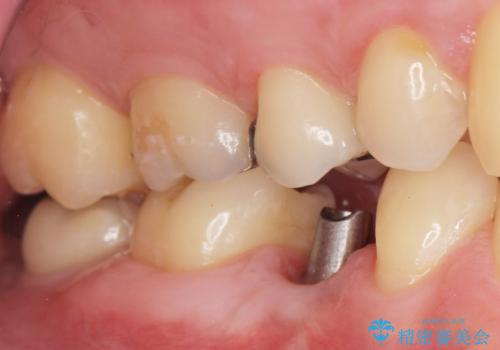

予算を抑えてしっかりとしたインプラント治療 30代男性

- 奥歯(右下5)のインプラントをご希望し来院された患者様です。

なるべく低予算でとのご希望により、アルファタイトインプラント(保証期間:3年)による治療を行いました。

自然な仕上がりと咬み心地に喜んで下さいました。

「低予算でしっかりした治療を受けることができた」とご満足頂けました。

インプラントの種類:アルファタイト

クラウンの種類:オールセラミッククラウン スタンダード